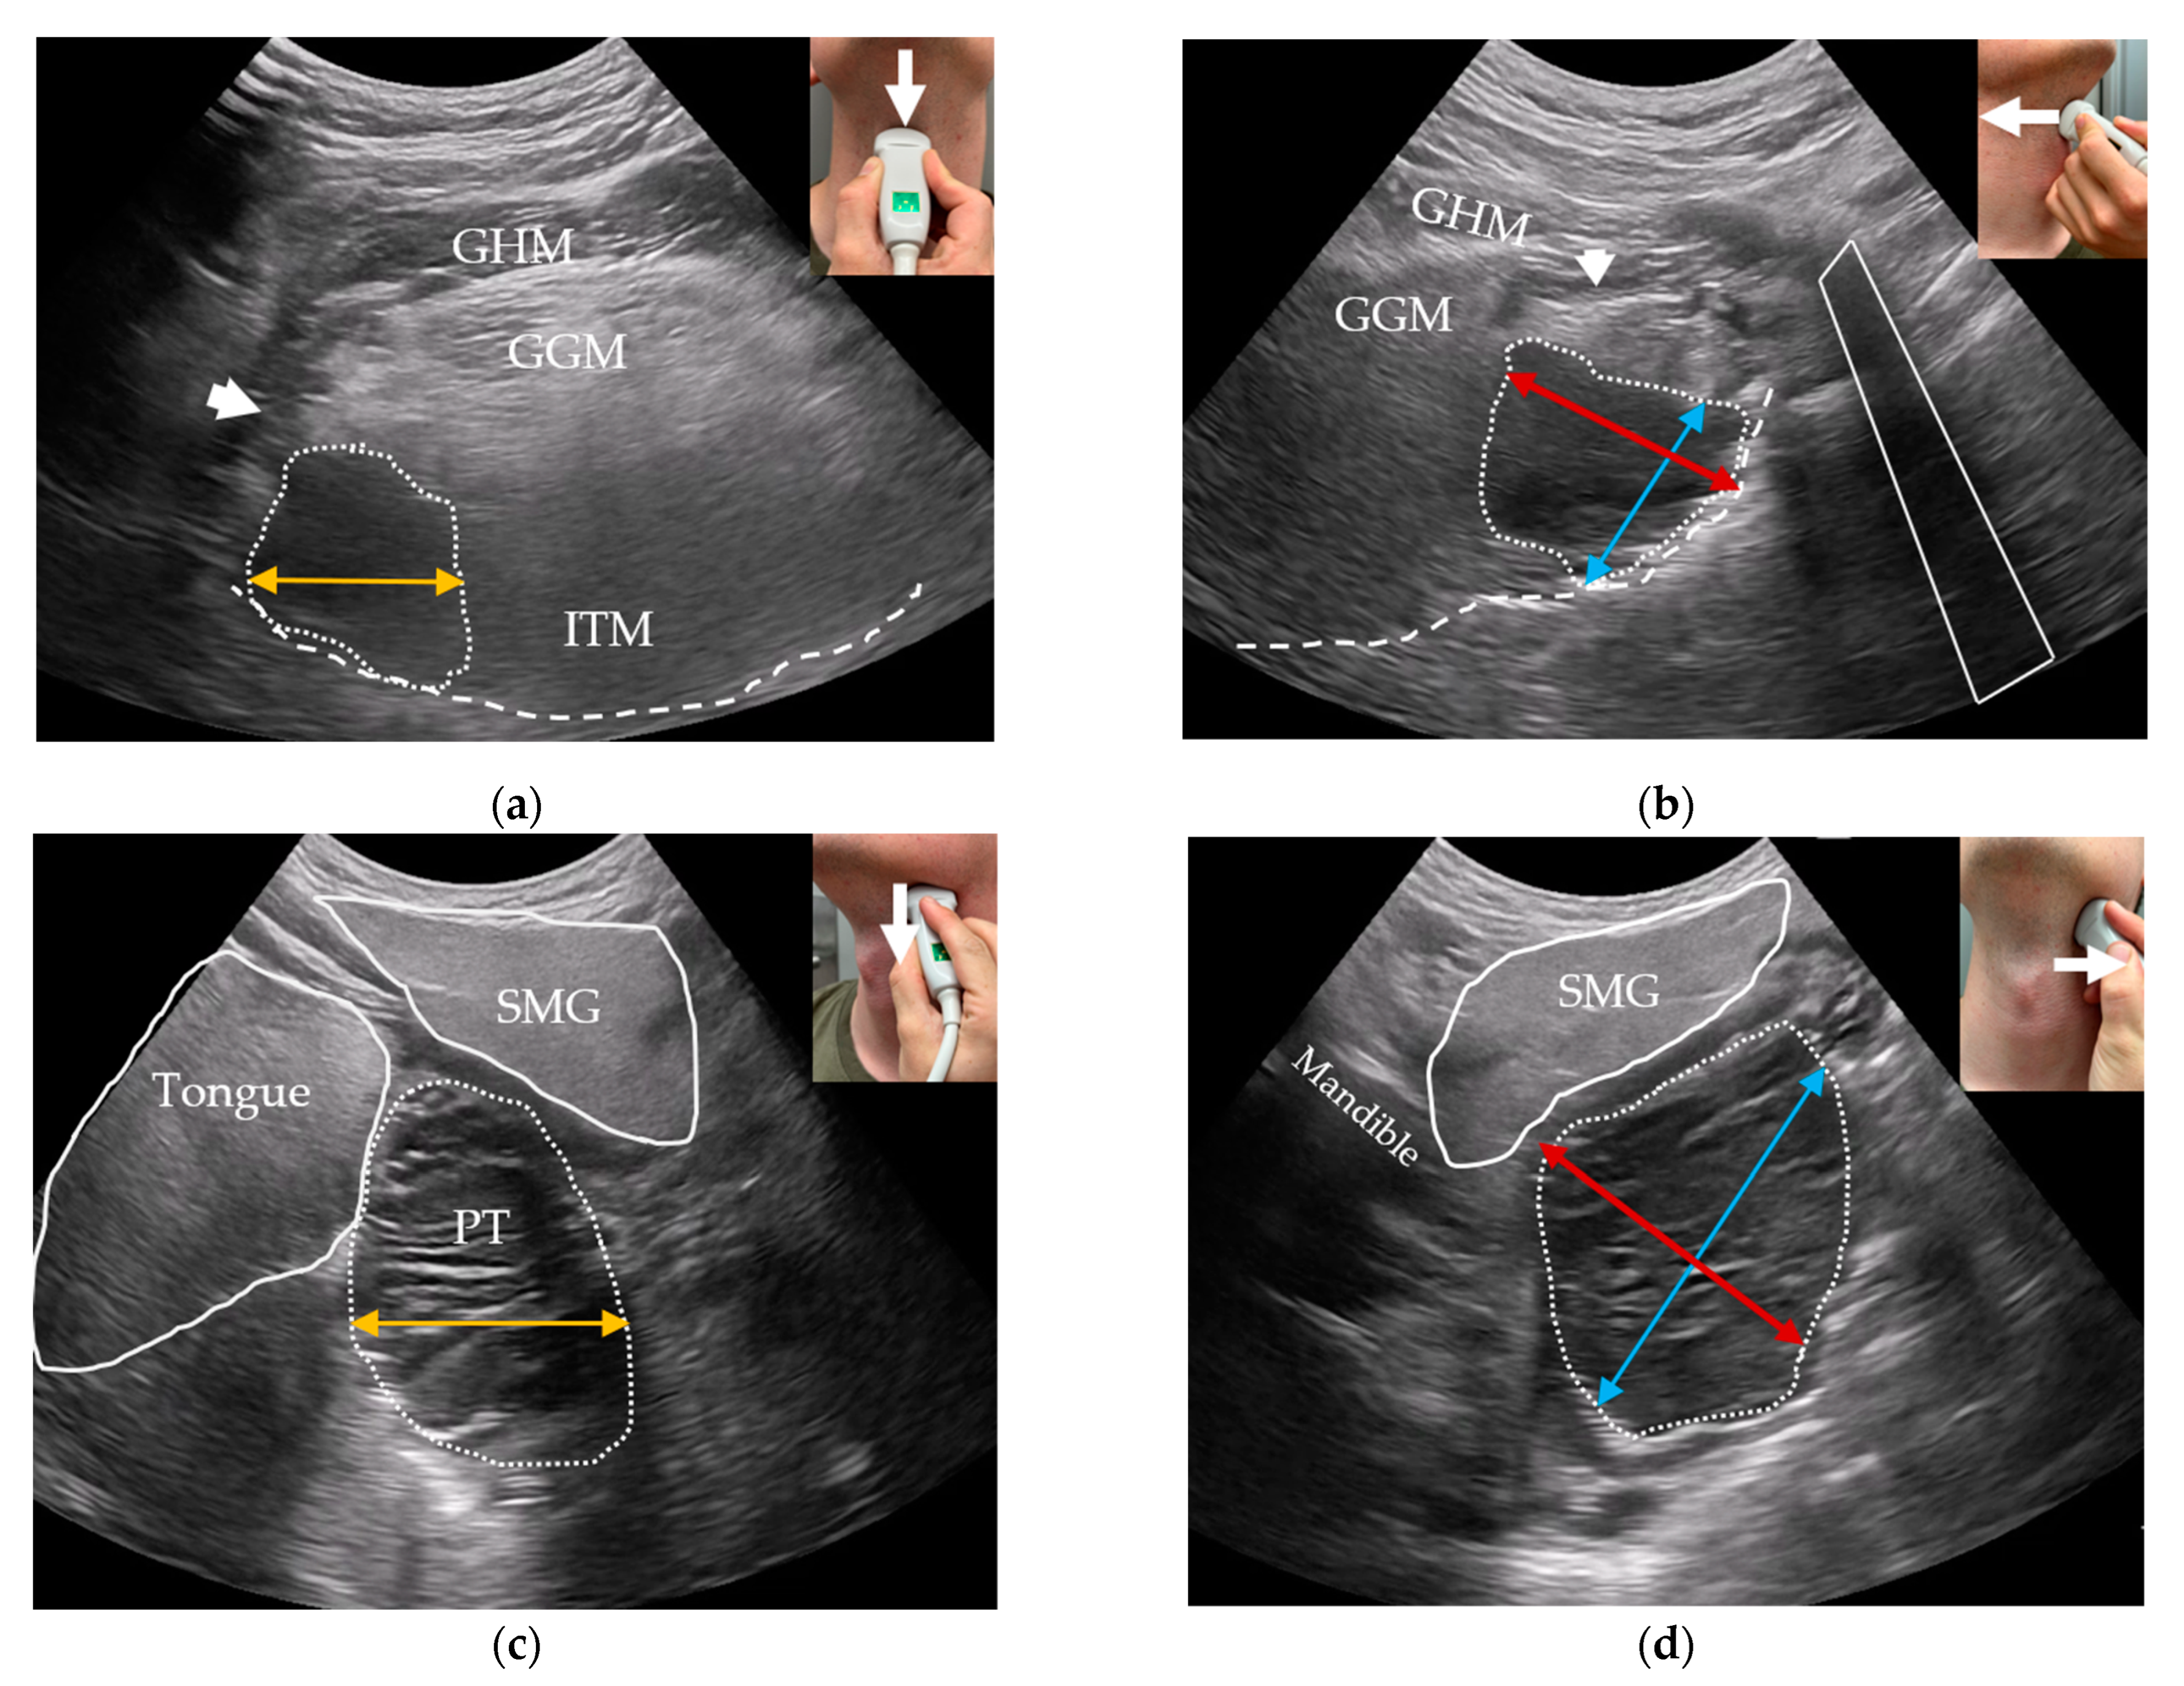

2.3.5. Outpatient-Performed Transcervical US

2.3.6. US Criteria for Tumor Detection

2.3.7. US Tumor Size Estimation and T-Staging